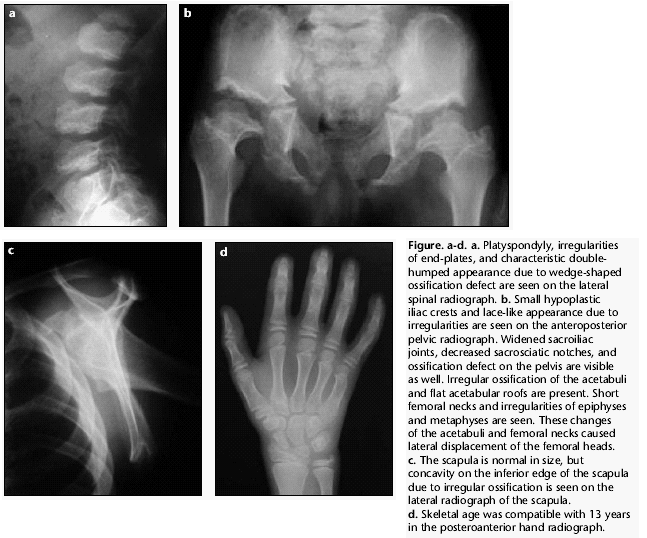

Синдром. Dyggve-Мельхиор-Клаузена синдром без задержки умственного развития (Smith-McCort дисплазия). +

Синдром.  Dyggve-Мельхиор-Клаузена синдром без задержки умственного развития (Smith-McCort дисплазия).